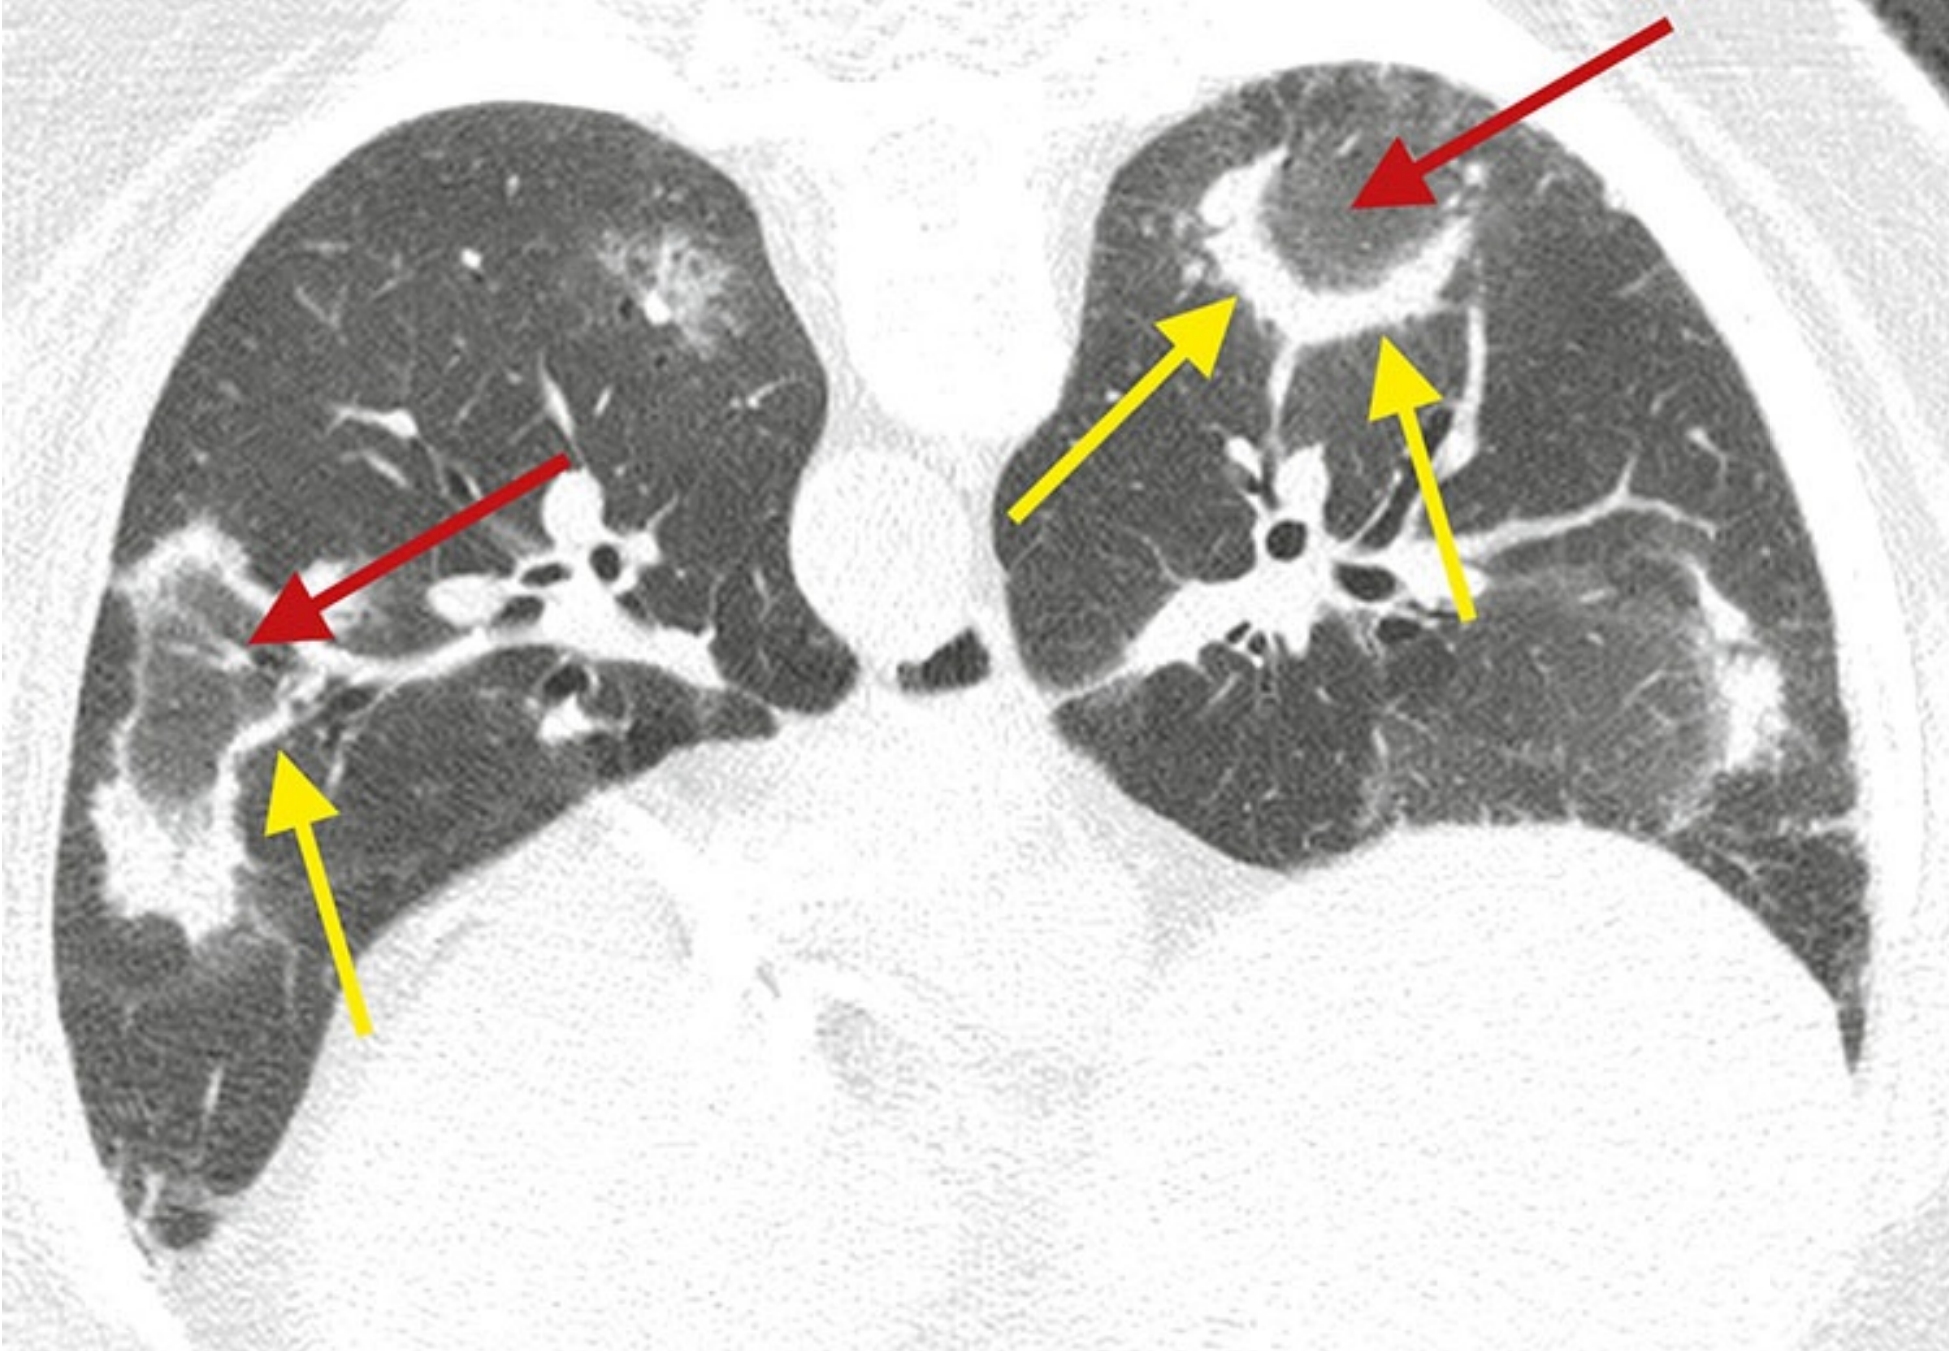

7331218b6857cead2350daf293806044.png

高置信度诊断为普通型间质性肺炎(UIP)的鉴别诊断。

4例UIP的HRCT表现;继发于特发性肺纤维化(A)、结缔组织病(B)、石棉沉着病(C)和药物中毒(D)的UIP, 均可见胸膜下及肺基底分布为主的纤维化伴蜂窝征。当表现为UIP模式时,上述疾病在HRCT上通常无法鉴别。